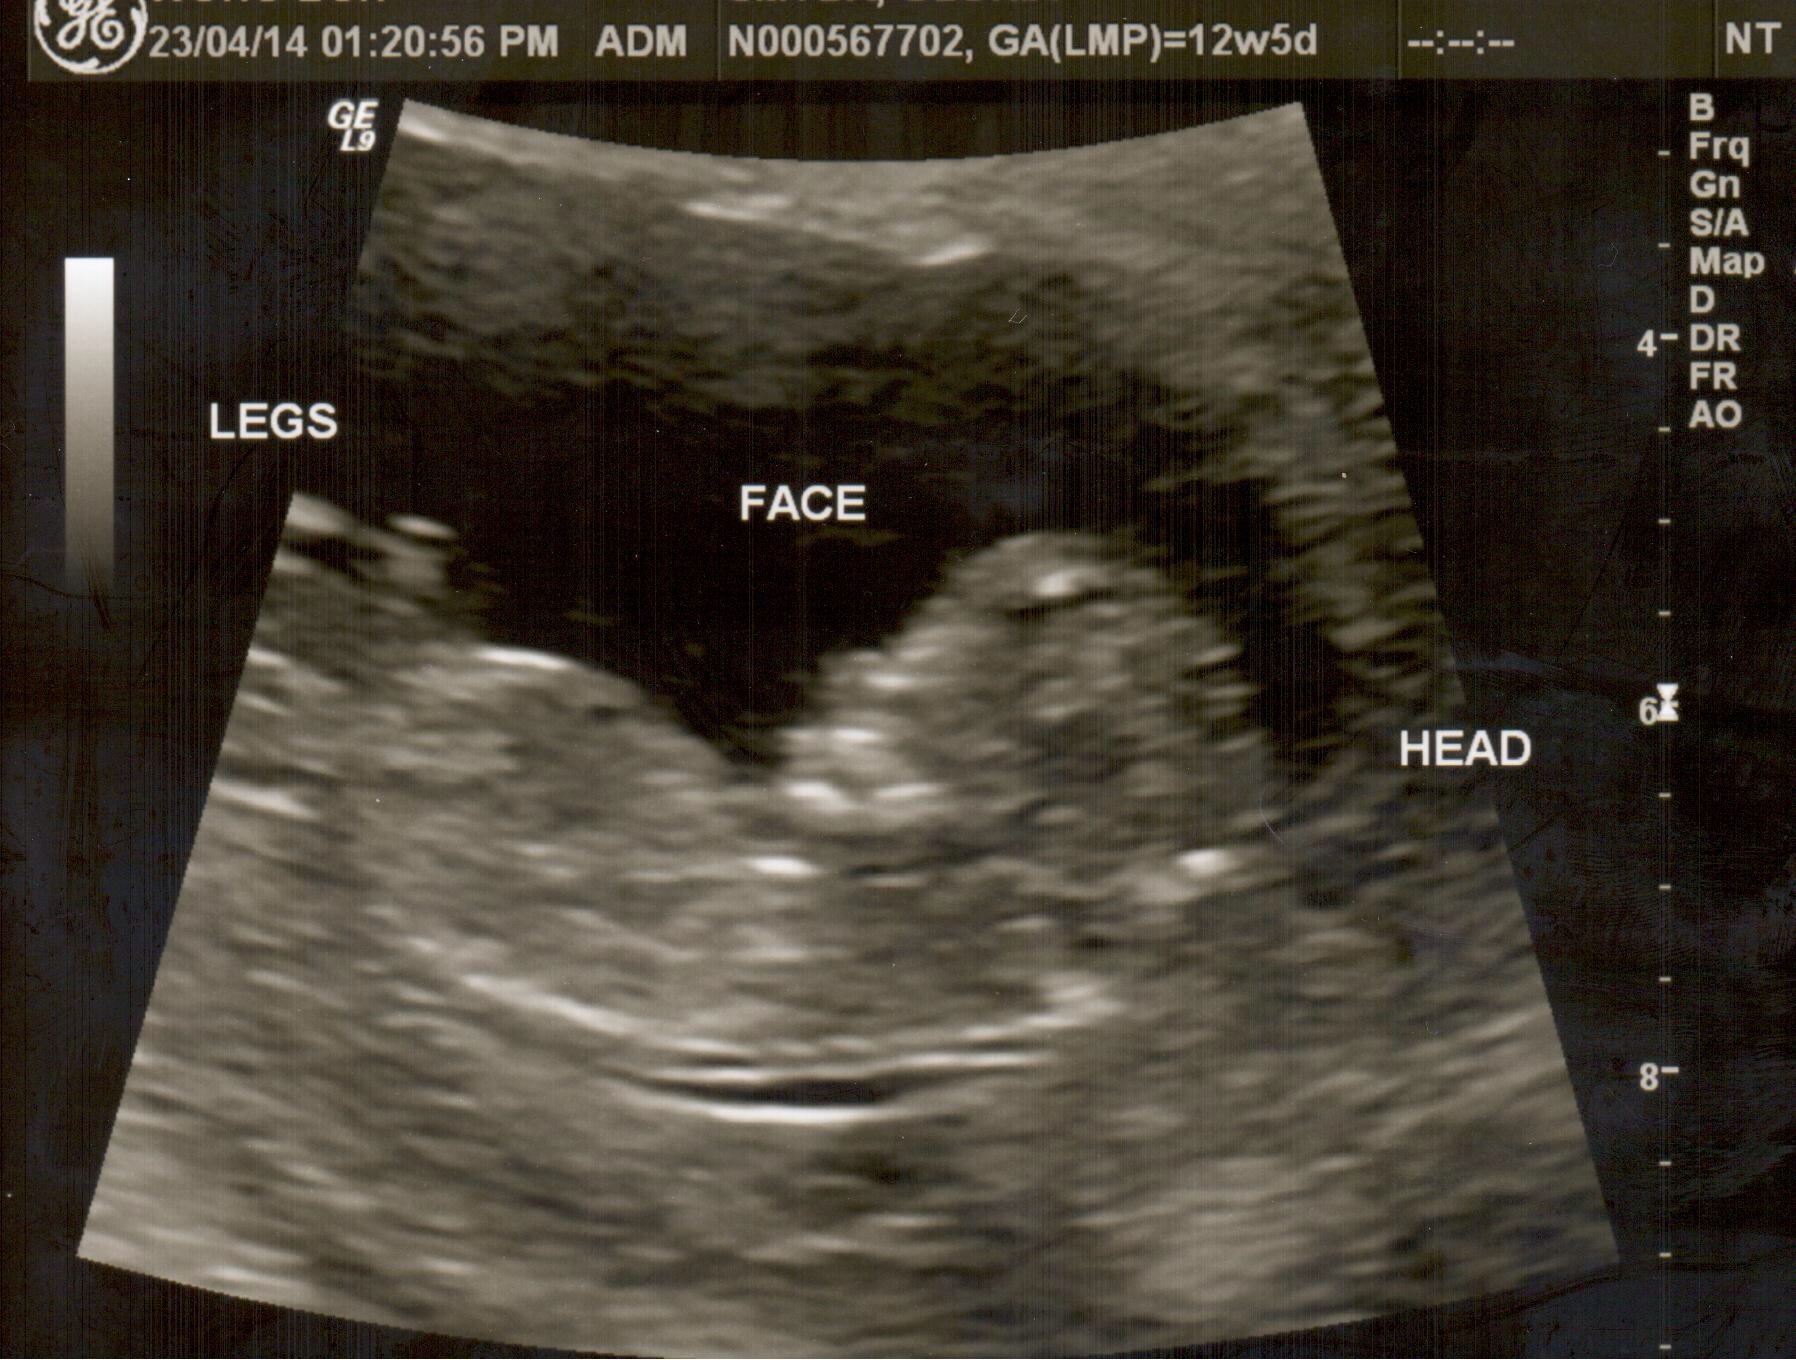

Had my NT scan today and didn't get to see between the legs. Dont think I see a nub in this pic but thought I'd post anyway. Does anyone see anything? Anyone know about skull theory?Attachment 18378

Sorry I don't see any nub and I'm not good at skull guesses. Bump!

Maybe girl xx